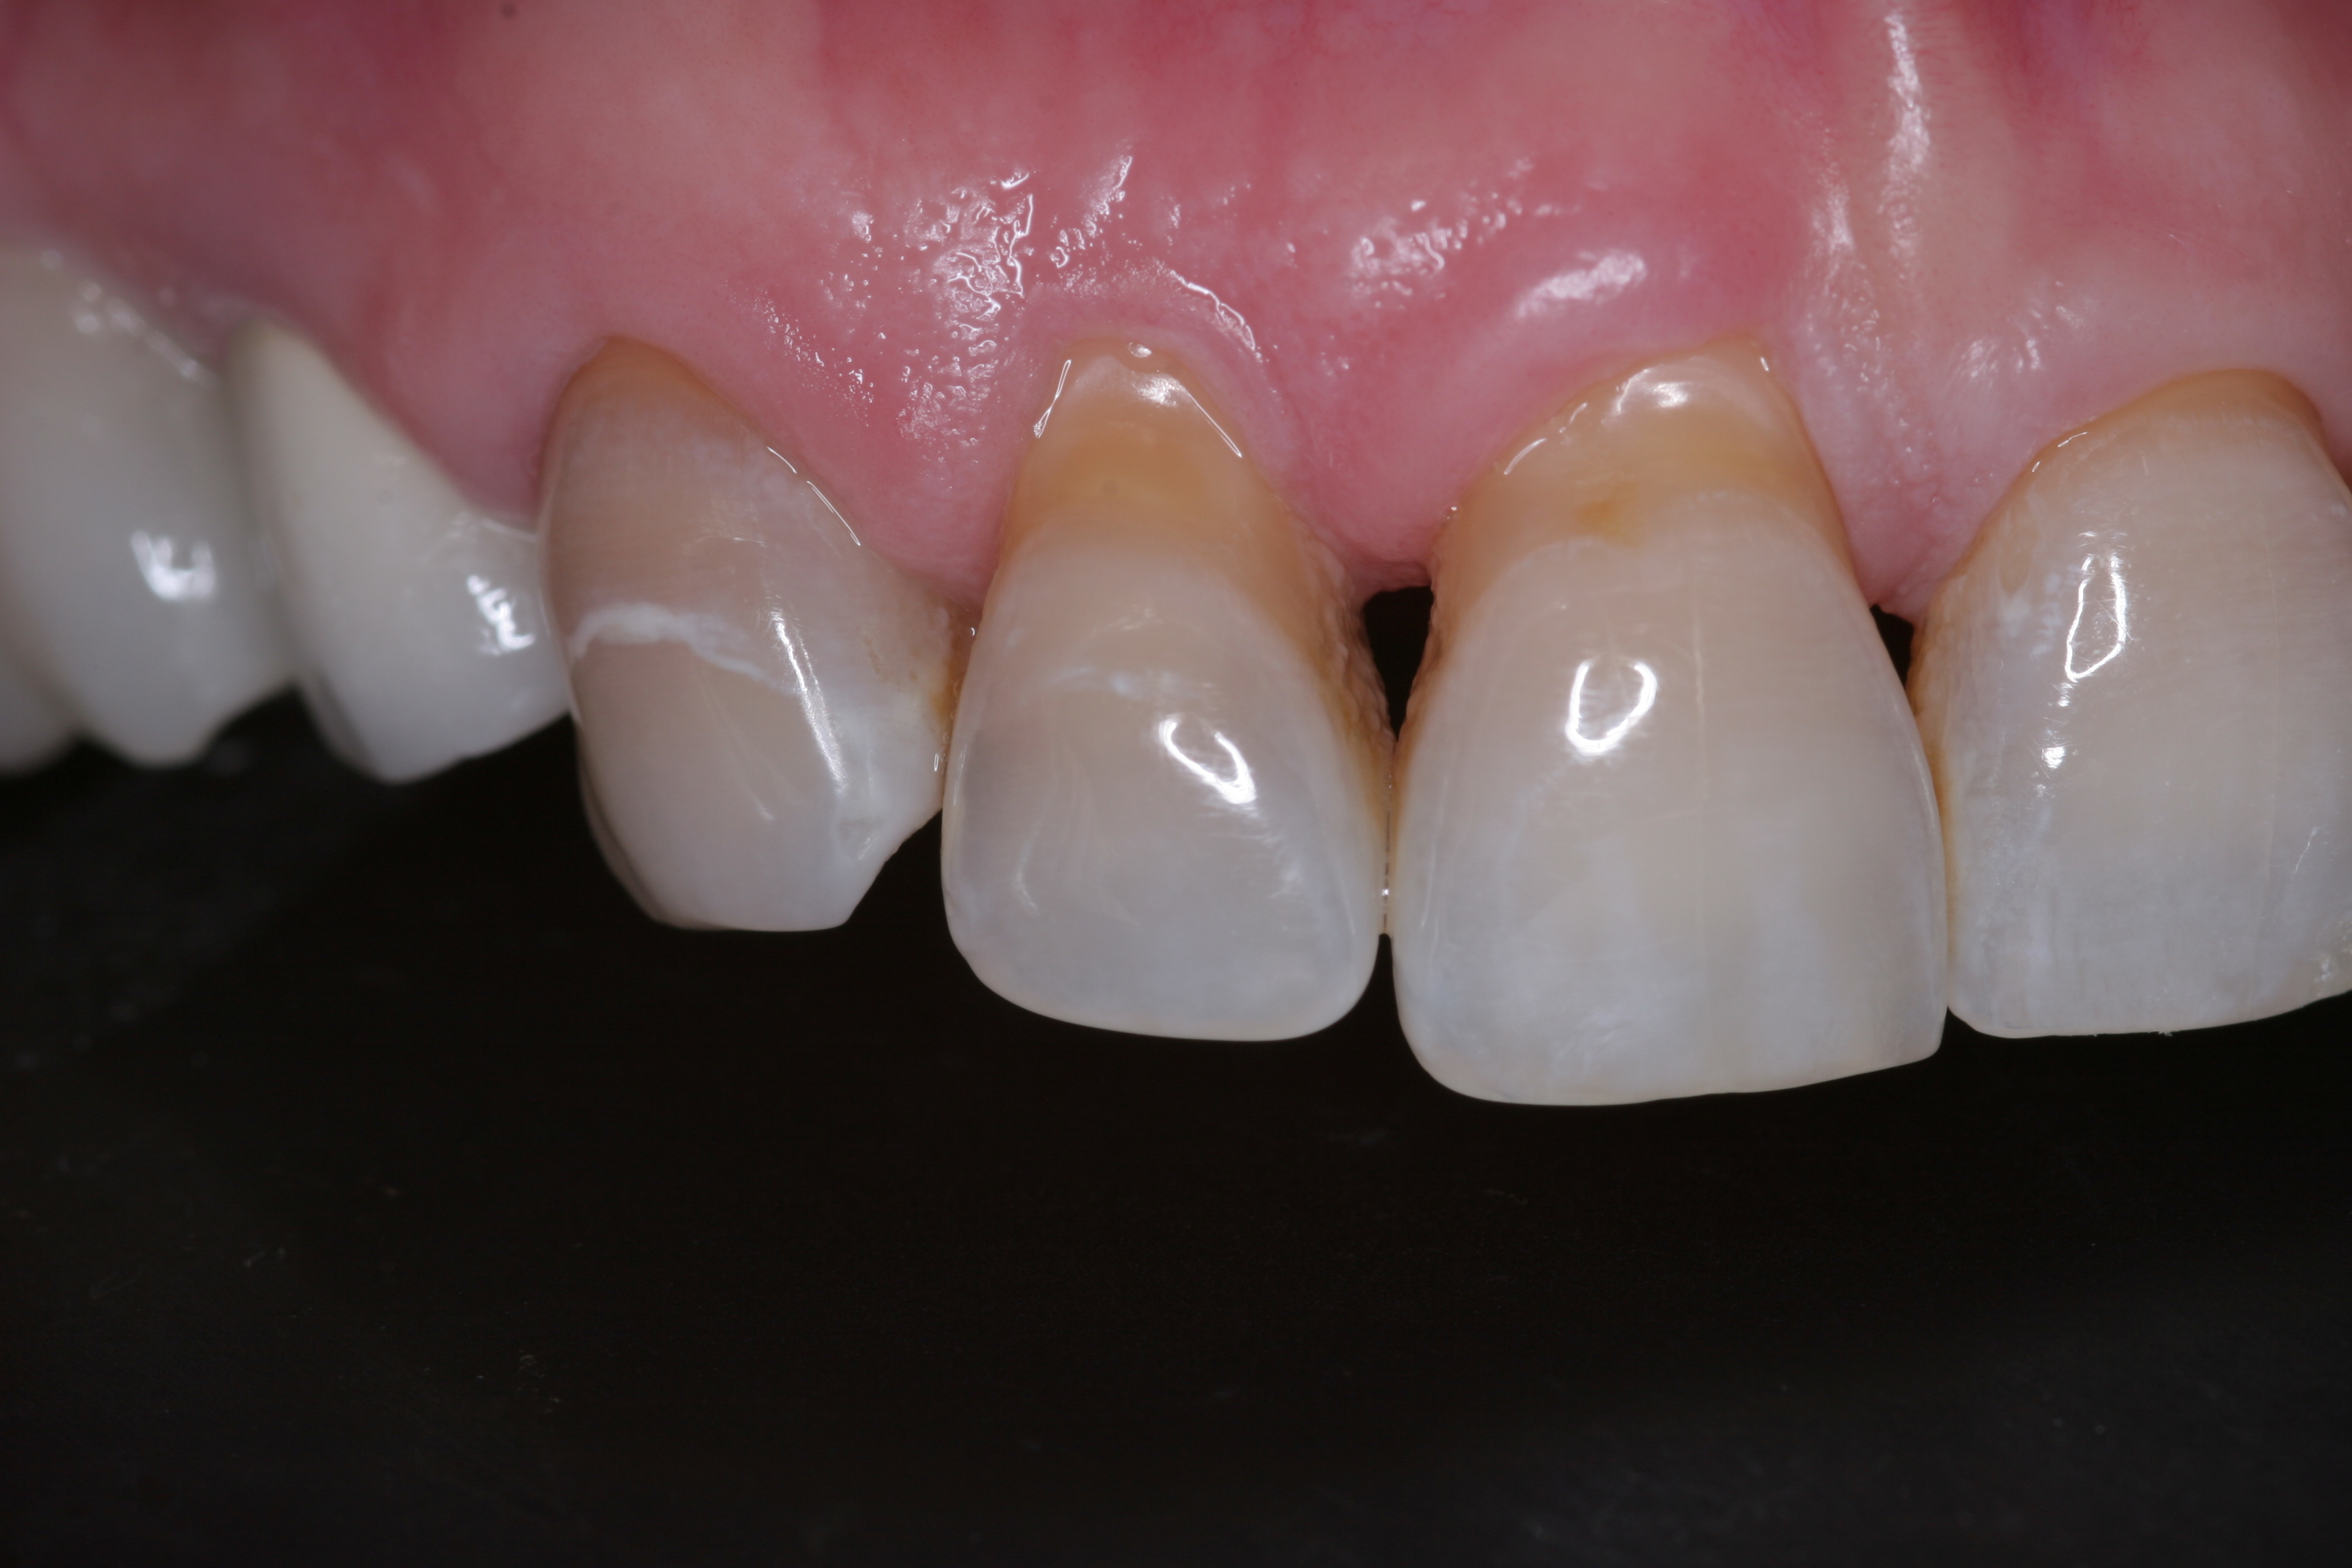

A patient presented with advanced generalized wear of her anterior teeth (Figure 10 and Figure 11). She was displeased with their overall appearance because of their color and wear (Figure 12). A complete examination was performed, revealing instability in her temporomandibular lateral poles bilaterally, sore muscles of mastication, advanced wear, a CR/MIP discrepancy, and loss of her anterior guidance due to the wear. Although the topic is beyond the scope of this article, the patient was also screened for possible sleep apnea. This included an evaluation of the Mallampati score, previous sleep therapy evaluation or treatment, snoring history, an evaluation of her neck size, her weight status, and the presence of the tonsils and their size. In every case, if this clinician suspects airway obstruction to be playing a role in tooth wear issues, the patient is referred to a sleep physician. The patient in this case displayed few apnea risk factors, and the patient’s anterior wear facets fit together like a “lock and key” pattern seen in parafunctional activity. Splint therapy was initiated to stabilize the joints and muscles. A repeatable CR position was verified through load testing. At this point diagnostic models, photographs, a CR bite record, and a facebow were taken and recorded.

(10.) A patient presented with advanced generalized wear of her anterior teeth, and was displeased with their overall appearance because of their color and wear.

(11.) A patient presented with advanced generalized wear of her anterior teeth, and was displeased with their overall appearance because of their color and wear.

Figure 11

(12.) A patient presented with advanced generalized wear of her anterior teeth, and was displeased with their overall appearance because of their color and wear.

Figure 12